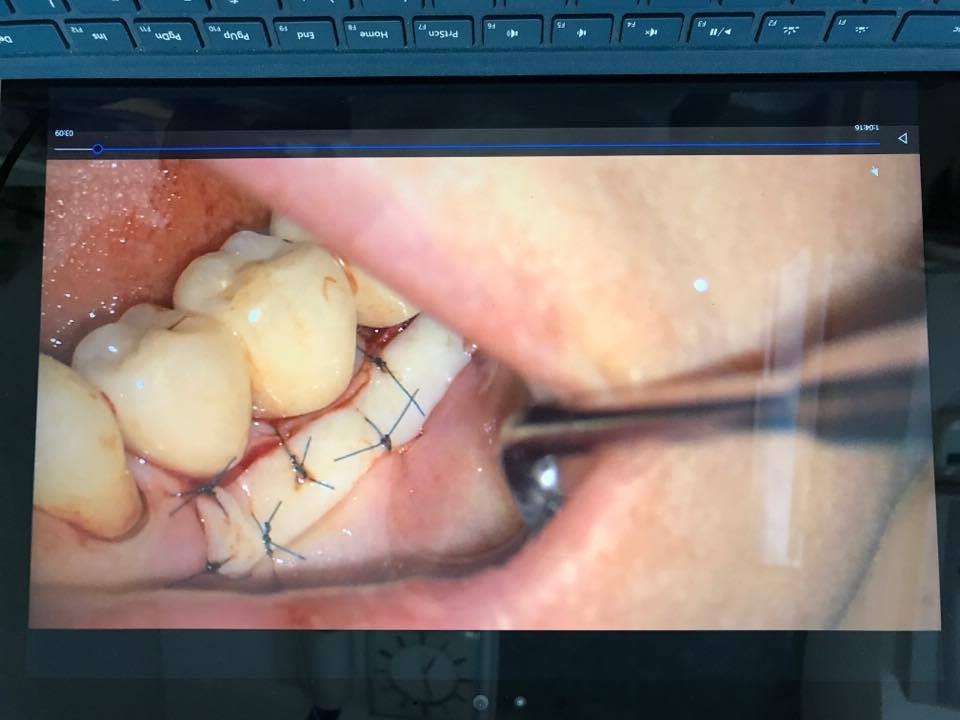

マイクロスコープを用いて上顎口蓋粘膜から採取した上皮付き粘膜を患部に移植することによりブラッシングしやすい環境にします。

第一歯科診療所では歯肉移植などの外科処置はマイクロスコープを使用するので術後の腫れや痛みが軽減し、またマイクロスコープ用の細い糸を使用するため治癒が格段に速く傷跡も目立たないようにすることができます。